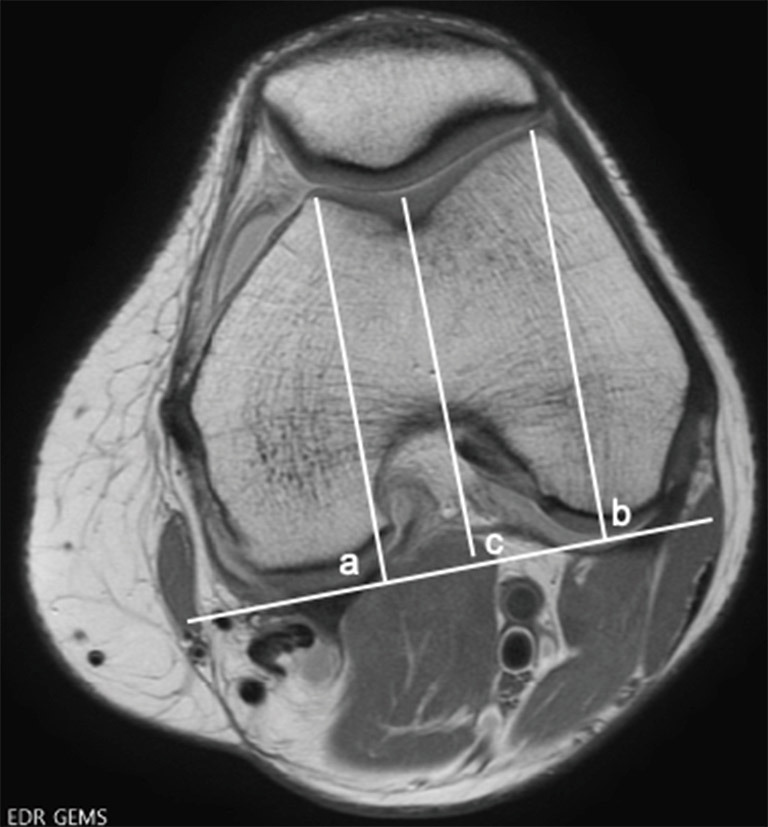

Patellar instability is a common clinical problem that primarily affects the adolescent and young adult population. The demographic and anatomic risk factors that predispose patients to patellar instability are multifactorial and include young age, female sex, trochlear dysplasia, elevated tibial tubercle to trochlear groove distance (TT-TG), patella alta, femoral and tibial malalignment, ligamentous laxity, and lack of neuromuscular control. There have been substantial efforts to predict which patients who sustain a first-time dislocation will go on to incur additional dislocations. This is particularly important because with each dislocation event, there is a significant risk of injury to the patellofemoral joint including both medial patellofemoral ligament (MPFL) stretch or rupture and damage to the cartilage which can range from simple fissures to full-thickness cartilage defects and osteochondral fractures. Prediction models have demonstrated that amongst first time dislocators, young patients with trochlear dysplasia are at the highest risk for redislocation. The current standard of care for treatment of first-time dislocators without a loose body or osteochondral fracture is nonoperative management. However, recently there has been a focus on implementing a risk-stratified approach to the surgical indications for a first-time dislocator as the high-risk population might be better treated with early surgical stabilization to prevent or reduce their risk of recurrent dislocation and its associated morbidity. Likewise, for patients with recurrent dislocations, it remains to be determined whether an isolated MPFL reconstruction is sufficient for high-risk patients with several poor prognostic risk factors or if bony realignment procedures should be implemented concurrently.